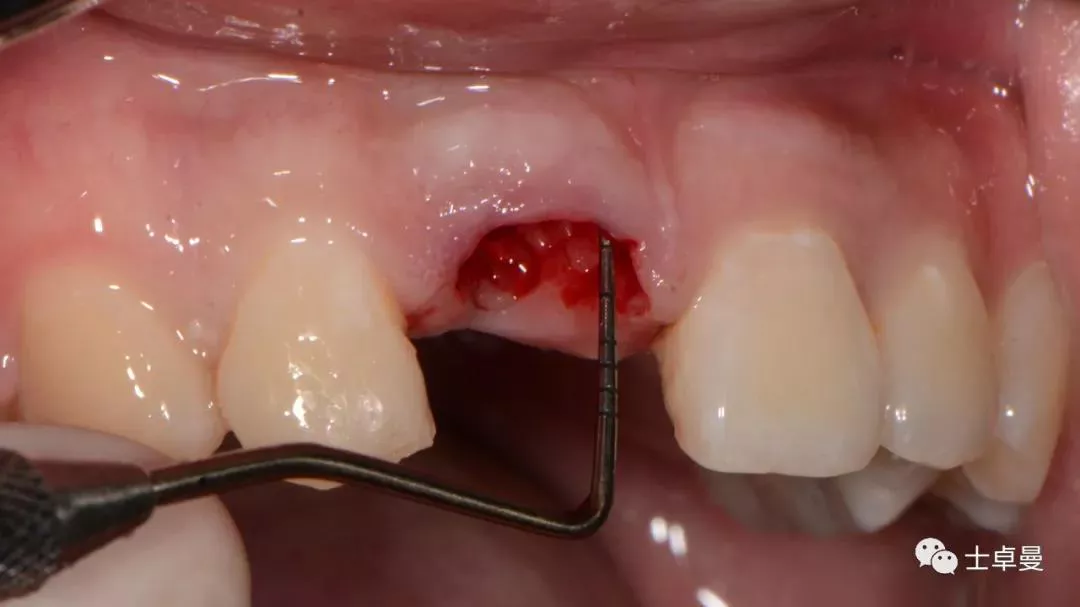

牙周探针探查牙片位置及松动度

就位种植外科导板

指示杆观察备孔三维位置

种植体植入后,植体唇侧间隙内填塞骨粉0.25g,胶原骨100mg,安放愈合帽,明胶海绵暂时封闭创面